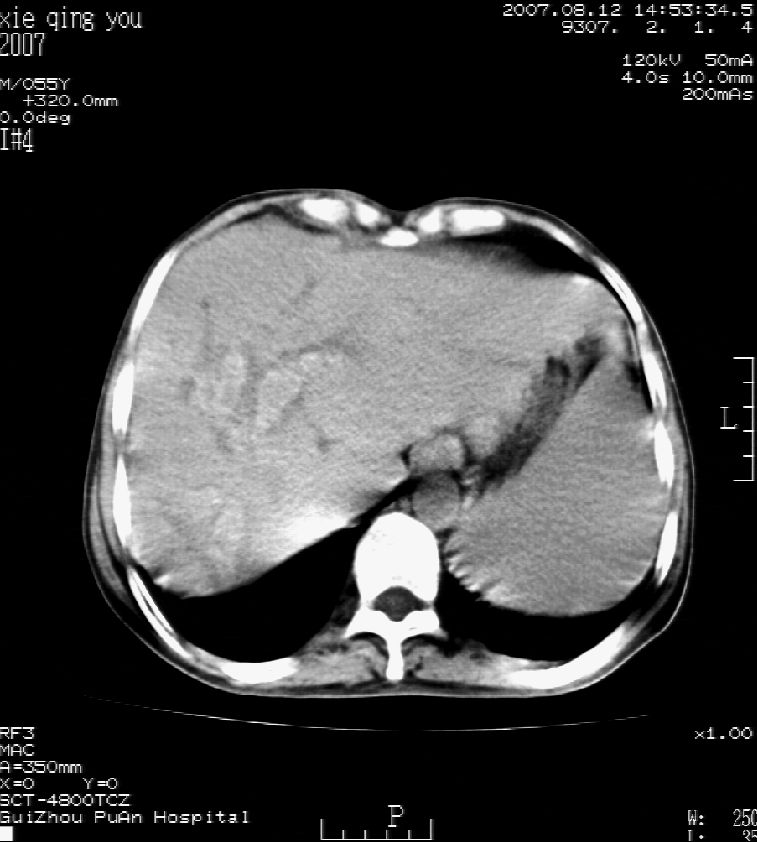

2007年8月片

这个病灶很有意思,怎么可能没有了呢?我考虑当时很可能是肝脏脓肿(b超示囊肿是有可能误诊的,因为影像表现都是低回声吗?),现在脓肿吸收了,肝脏萎缩,肝裂增宽了.别的肝叶代偿增大,不过现在左内叶的确有个占位,肝内多发结石,脾脏比以前大,不排除有肝硬化可能.建议增强扫描给于定性!!!!

肝硬化\\脾大,肝左叶肝癌可能性大,建议增强扫描.肝内胆管多发性结石.

1, 肝硬化,脾大;2,肝左叶肝癌可能性大,建议增强扫描.3,肝内胆管多发性结石.

肝硬化、脾大、肝内胆管多发结石。肝左叶低密度占位。建议增强扫描.排除肝癌